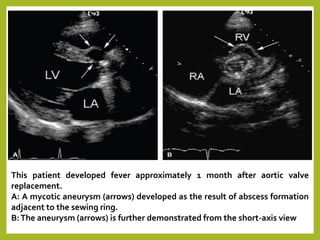

This patient developed fever approximately 1 month after aortic valve

replacement.

A: A mycotic aneurysm (arrows) developed as the result of abscess formation

adjacent to the sewing ring.

B:The aneurysm (arrows) is further demonstrated from the short-axis view